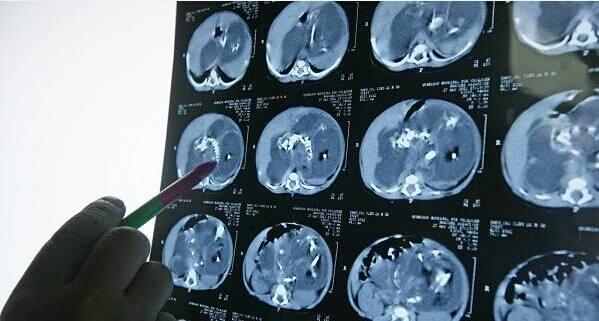

在孩子的腹部隆起到不正常的程度之后 , 李先生一家再也坐不住了 , 他们带着自己的孩子前往医院接受检查 , 结果却让他们大吃一惊 , 原来自己孩子的肚子里有一个寄生胎!寄生胎是一种先天性的疾病 , 这种疾病的发病率非常低 , 有科学研究调查显示寄生胎的发病率只有五十万分之一 , 李先生一家人痛苦不堪 , 心疼自己的孩子 , 但是医生告诉他们寄生胎的治疗方法只能通过手术 , 目前李先生的孩子已经恢复了健康 , 那么我们应该以李先生家的宝宝为一个借鉴 , 我们应该搞清楚寄生胎出现的原因 , 在宝妈孕期尽量的避免 。